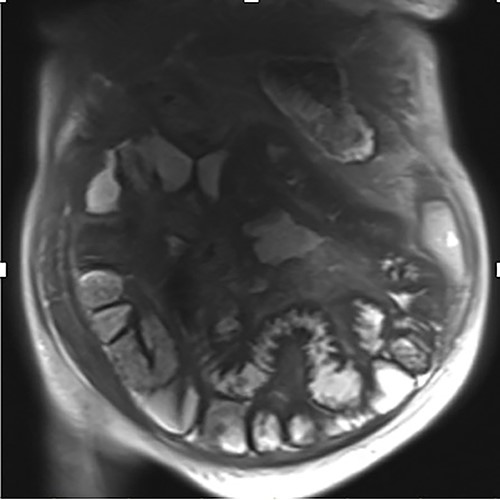

A 76-year-old lady presented to the outpatient clinic with a history of lower abdominal bloating and lethargy for 1 week. The patient denied abdominal pain, nausea, altered bowel habits or GI bleeding. Her past medical history included gastroesophageal reflux disease, ulcerative colitis and a previous hysterectomy. Physical examination exhibited pallor of the conjunctiva, distended abdomen with visible peristalsis on inspection but soft, non-tender on palpation and absence of ascites. Laboratory testing found normocytic normochromic anaemia, thrombocytosis and a positive myeloma screen with elevated kappa to lambda free light chain ratio despite normal renal and liver function. An ultrasound of the abdomen was unremarkable. Computed tomography (CT) with IV contrast of the abdomen revealed diffuse thickening of the small and large bowel with the small bowel dilated throughout. Magnetic resonance imaging of the small bowel showed multiple abnormally thickened loops of the jejunum and proximal ileum with a maximal wall thickness of 0.9 cm (Figs 1 and 2). Gastroscopy revealed severe distal oesophagitis, the stomach contained patchy telangiectasia and gastritis with sloughy mucosa at the incisura in addition to duodenitis with stricture at the second part of duodenum (D2) (Figs 3 and 4). Histopathology from the biopsies of the gastric incisura, D2 and the proximal jejunum displayed reactive changes with intramucosal haemorrhage and extensive deposition of pink amorphous, eosinophilic material on haematoxylin & eosin (H&E) stain. The deposits were predominantly seen in the proximal jejunum with a positive Congo red stain showing apple-green birefringence under polarized light (Figs 5 and 6). The patient was referred to Haematology, and a bone marrow aspirate and trephine biopsy revealed proliferation of 15% mature plasma cells consistent with the diagnosis of myeloma.

Coronal magnetic resonance image of abnormal thick-walled loops of jejunum and proximal ileum without focal stricture.